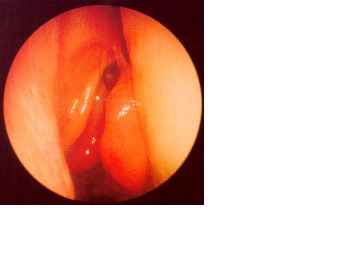

Material cadavérico inyectado. Imagen endoscópica de la pared lateral

del seno esfenoidal visualizándose por trasparencia la arteria carótida

intracavernosa. |